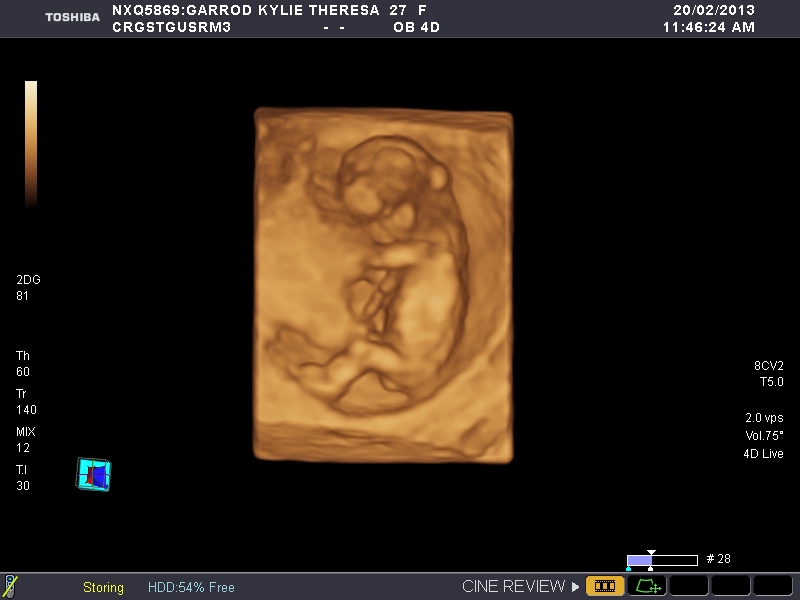

I dont think there are any gender clues Maybe Skull Shape if you would like to base a guess on that, but I'ld like to share my baby with the world anyway.